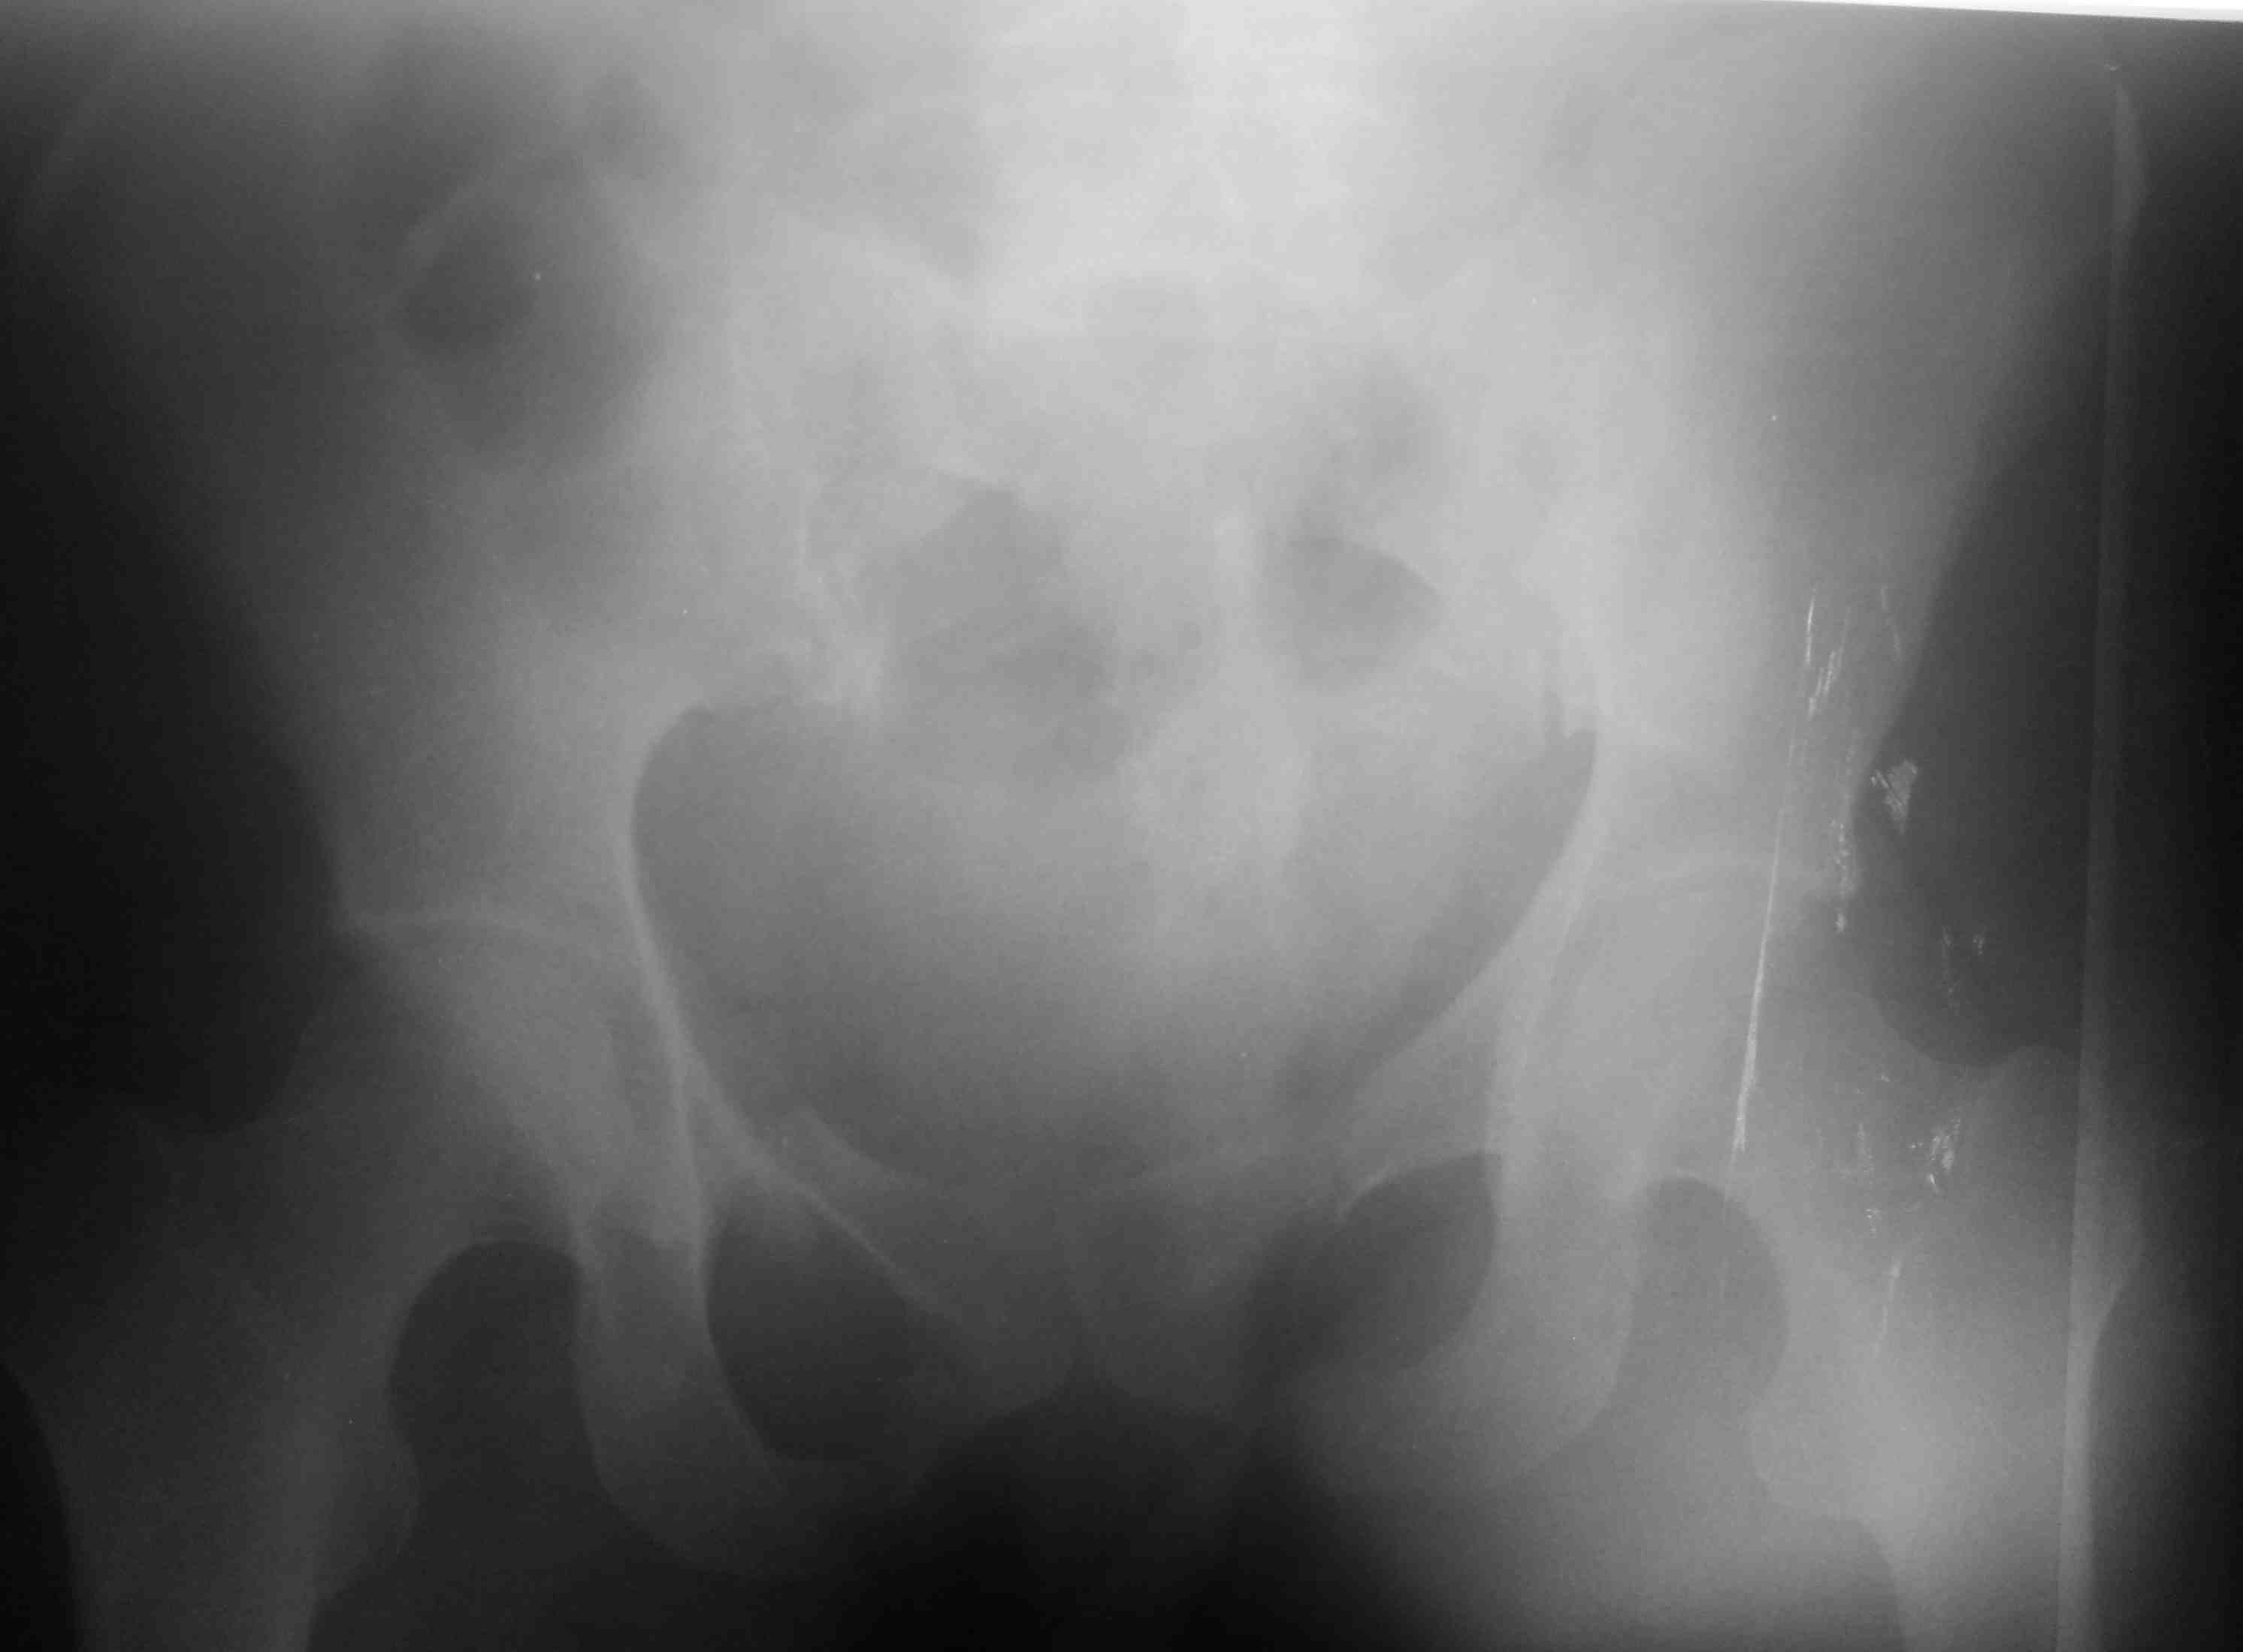

высылаю контрольные снимки на вытяжении, правую половину таза подрепонировали вручную, за лево - скелетка. Дополнительно, левое плечо - диафиз, множественные переломы ребер слева. Стала хуже по легким. Пока план - при улучшении по легким - передняя рама + илиосакральные винты справа, при улучшении - расслабляем переднюю раму, открыто синтезируем подвздошную кость задним доступом, обратно затягиваем аппарат. Плечо - когда получится